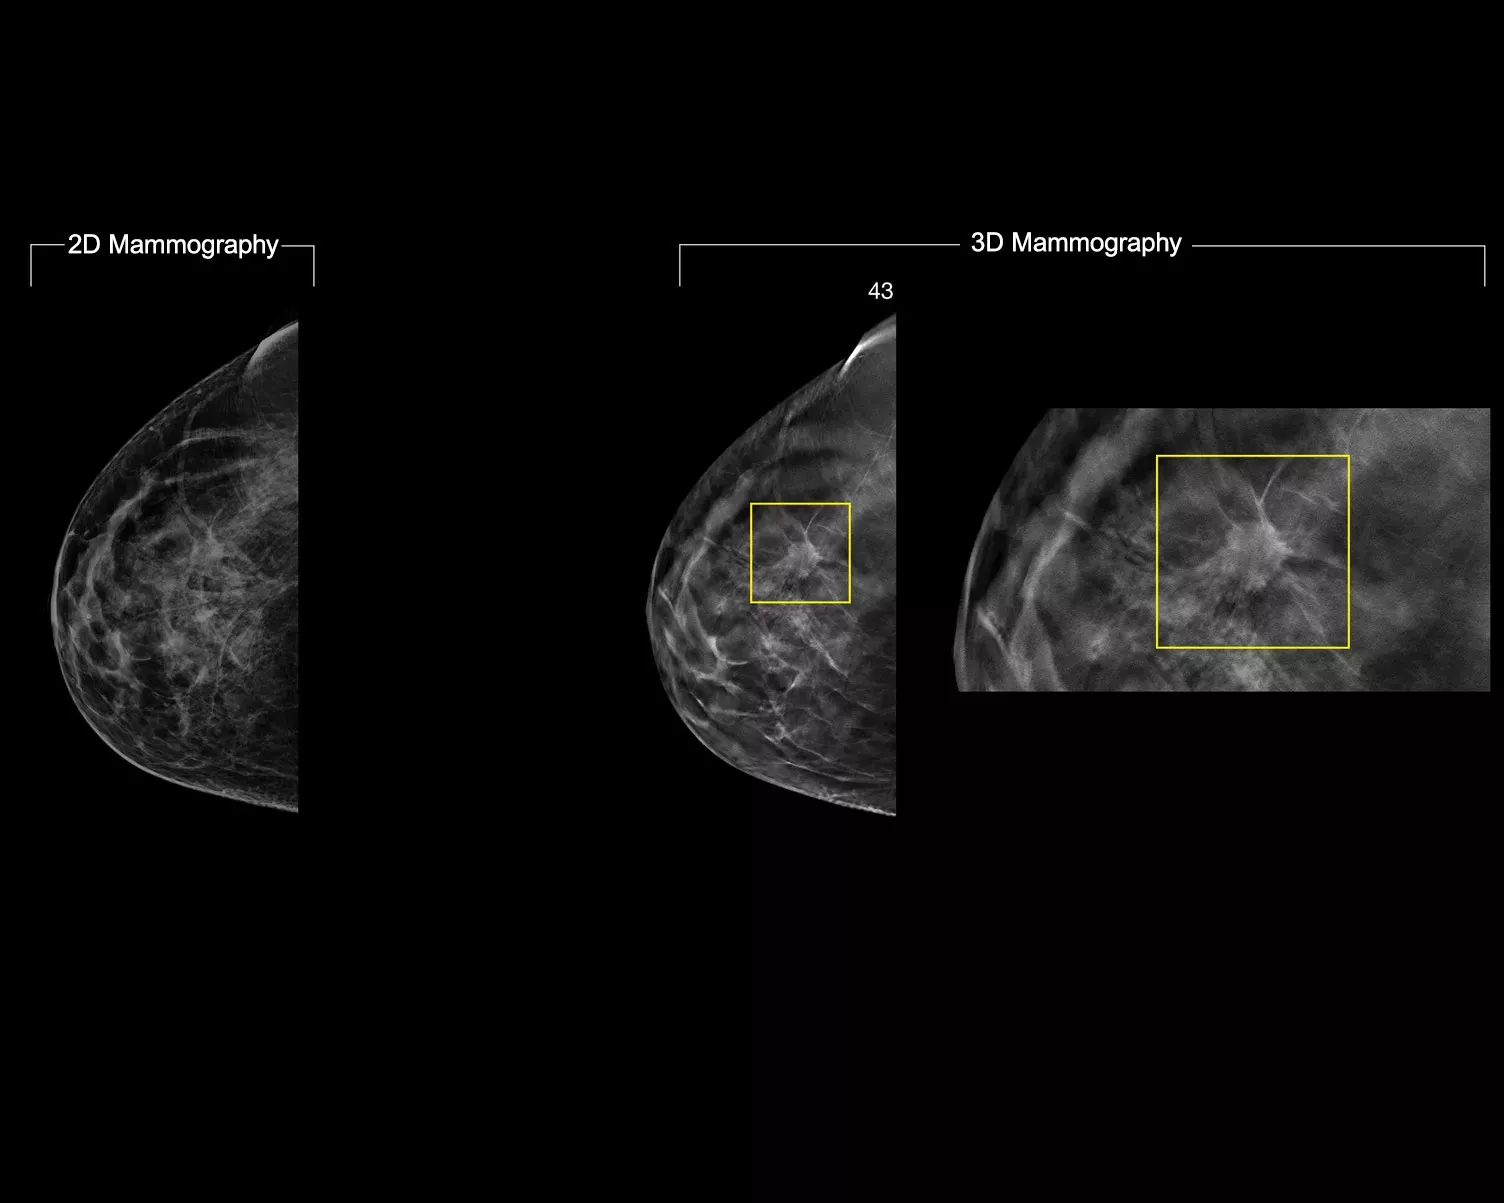

A deep-learning algorithm designed to aid radiologists' diagnostic performance and detect breast cancer1-3 from tomosynthesis images obtained using the Hologic Dimensions Mammography® Systems. The algorithm locates lesions that are likely to represent breast cancer by searching each slice of the tomosynthesis image set. The suspicious areas are highlighted for concurrent reading at the radiologist's workstation to aid in interpretation.

Study shows +9% improvement in observed reader sensitivity for cancer cases.1.2 Works on standard and high-resolution tomosynthesis images; overlay on 3DQuorum SmartSlices and synthesised 2D images.

The algorithm looks for 3 main groups of suspicious lesions: calcifications, masses, densities and distortions, and any combination of these lesions. Outputs may vary on different reading workstations.